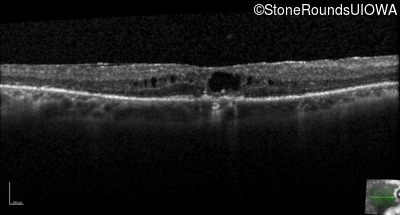

Age at visit: 66 years

OD OS